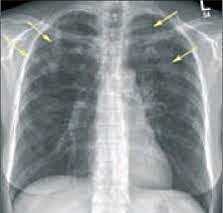

• Рентгенологические исследования. На рентгенографии органов грудной клетки можно выявить признаки уплотнения легочной ткани в виде сетчато-узелкового или сетчатого поражения. Там же обнаруживаются признаки плеврита и изменения контуров сердца при гидроперикарде. Рентгенография не является основным методом диагностики, поскольку патологические изменения выявляются лишь в 20% случаев синдрома.

- Рентгенологические исследования. На рентгенографии органов грудной клетки можно выявить признаки уплотнения легочной ткани в виде сетчато-узелкового или сетчатого поражения. Там же обнаруживаются признаки плеврита и изменения контуров сердца при гидроперикарде. Рентгенография не является основным методом диагностики, поскольку патологические изменения выявляются лишь в 20% случаев синдрома.

- Рентгенография легких. На снимках видны субплеврально расположенные одиночные (реже множественные, двусторонние) нечеткие затемнения средней интенсивности неправильной формы размером до 3-4 см. В окружении инфильтрата легочный рисунок усилен, тень корня легкого слегка расширена. Характерна быстрая динамика инфильтратов с миграцией по легочным полям и исчезновением не позднее 1-2 недель после обнаружения (чаще через 1-3 дня) без остаточной рубцовой деформации. При длительно поддерживающемся инфильтративном воспалении в ткани легких могут образоваться фиброзные очаги и кистозные полости.